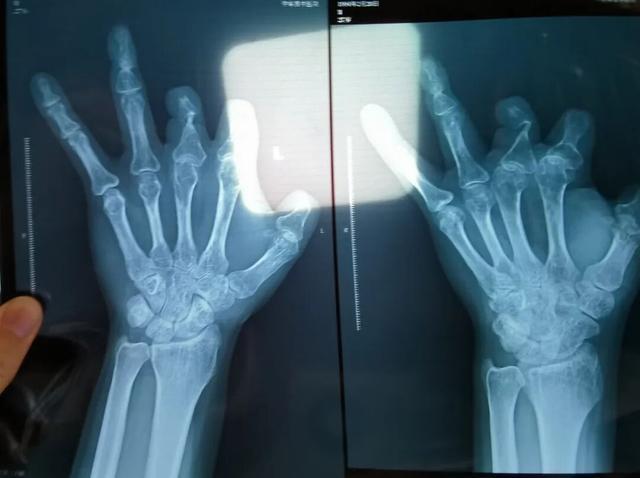

单价1.68万元,声称在术中植入体内、用于缝合血管的两个环形吻合装置,竟然在王海森的X光片上消失了。

患者王海森左手拇指关节以上部位被电锯切断,收费单显示术中使用了微血管吻合装置,但X光片中未显示该器械。新京报记者 程亚龙 摄

该产品的代理商曾向新京报记者证实,微血管吻合装置为植入型医疗器材,患者拍摄X光片时会有显示。新京报记者获取了一位曾在郑大一附院接受手术、使用了该产品的患者的X光片,其手术部位可见一绿豆大小的光圈。

装置上带有不锈钢针,不可能被人体吸收,唯一的可能就是“手术时其实没有使用”。尽管之前也有其他人向王海森透露过这一点,但直到看到片子前,他一直都不相信。